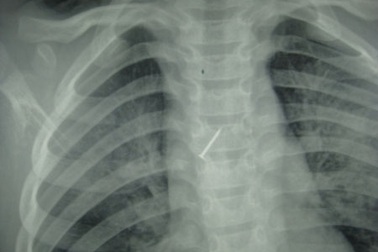

Đinh ghim sắt chui tọt vào phế quản bé gái 12 tuổiTrong lúc đang chơi đùa với em ở nhà, bé gái 12 tuổi (Sơn La) nhặt được chiếc đinh ghim sắt vốn dùng để ghim giấy, liền cầm nghịch chơi. Trong lúc ngậm ở miệng sơ ý cô bé đã nuốt phải chiếc ghim này.